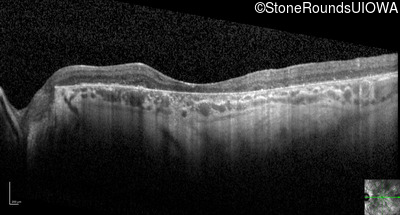

Optical Coherence Tomography - Left - 10/225

Exemplar / OCT Stack